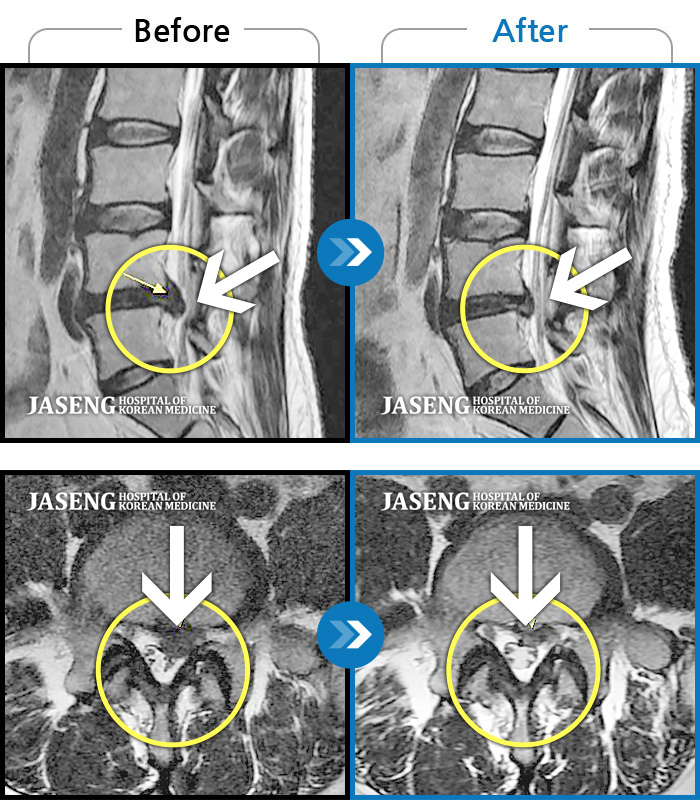

40대 초반 여성 환자인데요,, 처음 선생님 뵈었을 때에 1번,4,5번허리디스크 증상도 증상이지만,

본인 나이에 비해서 10~15년정도 퇴행이 많이 되어있어서 전체적으로 관리가 많이 필요하다고 설명해주셨구요,,

그당시 원장님진료실에서 보았던 저의 엠알아이사진이 아직도 생생히 기억이 납니다 ^^

뼈부분의 색이 왜저렇게 검냐고 여쭈어 보았더니, 말씀주신데로 "퇴행이"많이 되어서 그렇다고 설명해주시면서,,

그렇다고 당장 크게 머가 안좋거나 그런건 아니고,, 퇴행된 뼈자체를 새것으로 되돌릴수는 없지만,,

꾸준히 치료받으면서 관리만 잘한다면 건강한 뼈를 가진 사람과 동일하게 건강한 생활 충분히 가능할수 있다고,, 긍정적으로 말씀을 주셨어요...